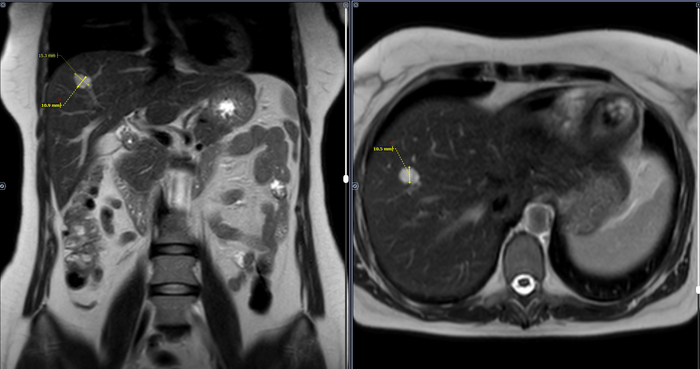

Структура печени неоднородная, за счет наличия в VIII сегменте правой доли дополнительного образования размерами 1,0х1,5х1,0 см, неправильной формы, с четкими неровными контурами, однородной структуры, повышенной интенсивности МР-сигнала в Т2 режиме, повышенного сигнала на высоких значениях b-фактора в режиме DWI и высокого сигнала на ADC-карте, с постепенным центрипетальным типом контрастирования. Заключение: МР картина образования (гемангиомы) правой доли печени.